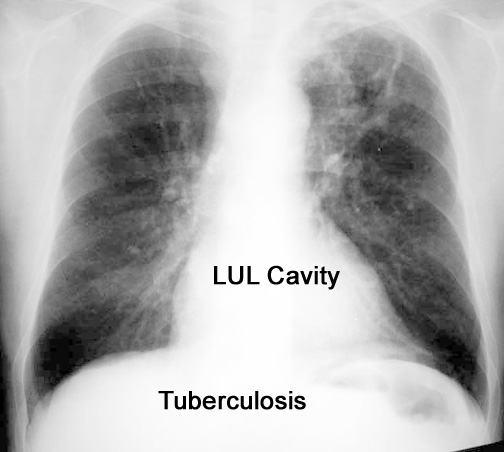

Case 15 Labeled Image What are the characteristics of tuberculous cavity?